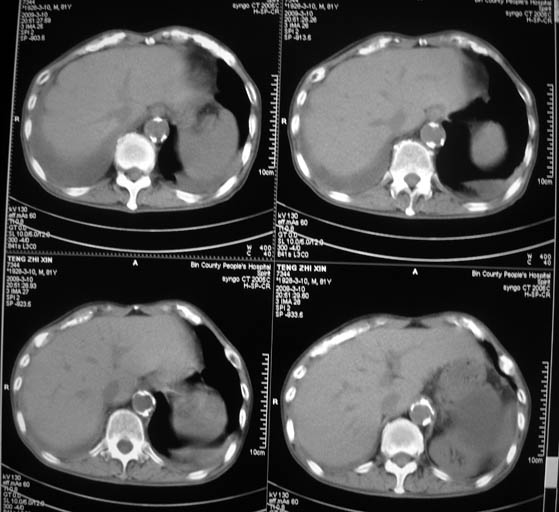

标题: CT18642:男,81岁,发热待查。

男,81岁,发热待查,右侧是占位还是膈疝?

右肺中央型肺癌并两侧胸水,左肺转移,腹水

1)考虑右肺下叶中央型肺癌并左肺转移。2)两肺上叶结核(陈旧性)。3)双侧胸腔积液。4)腹水。

右中央型肺癌并双肺及胸膜、肝脏转移

右中心型肺癌并双肺及胸膜、肝脏转移!

右肺中心型肺癌,胸、腹水